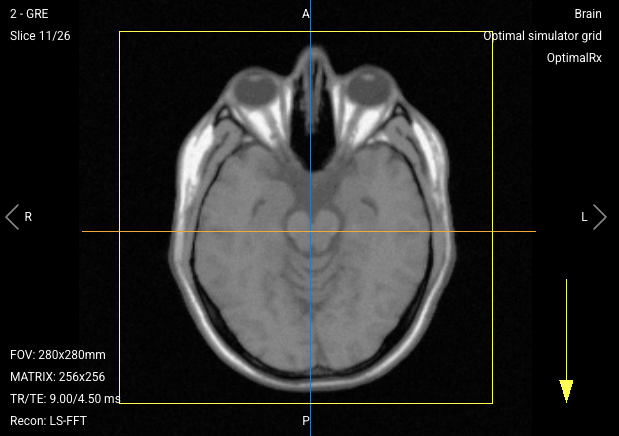

- The Phase Encoding direction is always indicated by a yellow arrow on the viewport.